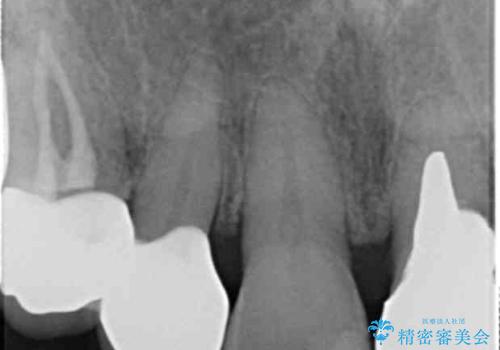

- 前歯が欠けたとのことで来院。

確認すると上の前歯の裏側に大きな虫歯がありました。

- 右上2 仮歯+ジルコニアクラウン(スタンダード) 11000円+110000円費用は治療当時の料金となります

歯と歯の間の大きなすき間と虫歯の両方を解決することができ、大変満足していただけました。